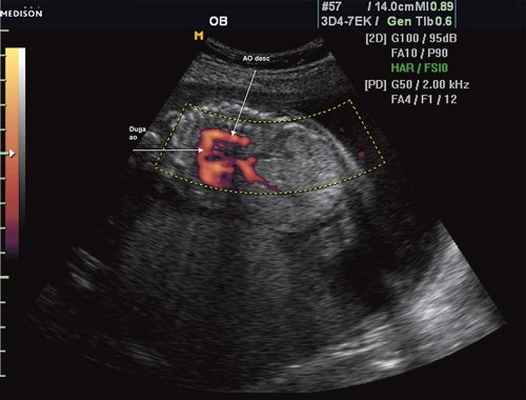

Рис. 3. Трехмерное изображение сердца и аорты плода в 16 нед беременности. Стрелкой указано место сужения аорты. AO DESC - нисходящий отдел аорты, COR - сердце.

Исходя из особенностей внутрисердечной гемодинамики плода, для диагностики коарктации аорты были предложены косвенные признаки патологии в антенатальном периоде: дилатация правого желудочка и его гипертрофия (см. рис. 3), дилатация легочной артерии [6, 7, 14]. Авторы считают, что это достоверные признаки и встречаются они достаточно часто (в 18 из 24 случаев верифицированных диагнозов коарктации аорты). Поэтому была предложена оценка индексов отношения полости правого желудочка к левому (в норме - 1,1) и легочной артерии к аорте (у здоровых - 1,2). Исходя из увеличения этих параметров, можно предположить наличие затрудненного выброса в аорту или гипоплазию дуги аорты. Тем не менее, по данным предложивших эти косвенные признаки авторов, такие изменения выявляются только в 30% наблюдений (рис. 4).